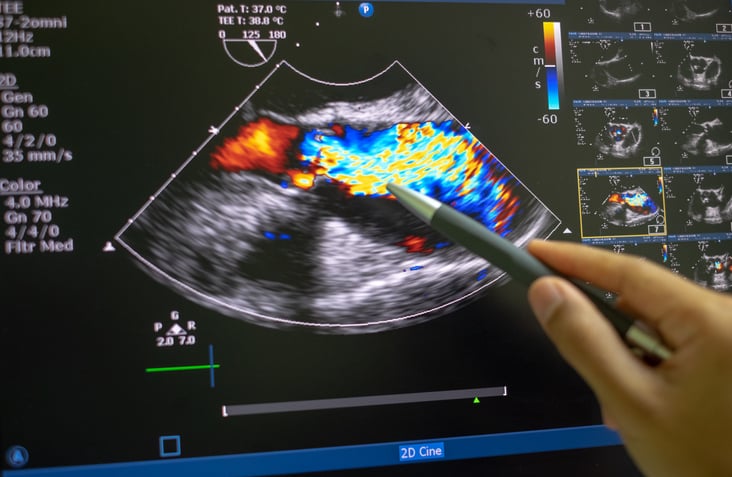

Questi pazienti spesso fanno più coronografie, inutilmente, sempre con il medesimo esito. Anche nel caso dell’infarto del miocardio del tipo Minoca il medico, non essendo spesso in grado di stabilire la causa, è in difficoltà a prescrivere le cure più appropriate. Nessun varco nel “mistero” dell’invisibilità delle cause? «Adesso sì – risponde il professor Saia – disponiamo di raffinate tecniche di fisiologia coronarica e/o di imaging che ci permettono di vedere più a fondo e arrivare, anche se non sempre, a diagnosi corrette e, dunque, a cure appropriate. Ora sappiamo che in una buona percentuale di casi il disturbo che provoca Inoca e Minoca riguarda il microcircolo. I piccoli vasi non sono in grado di dilatarsi completamente per aumentare il flusso sanguigno. Oppure sì, sono colpite le arterie, avvengono spasmi delle coronarie con un restringimento significativo dei vasi che procurano dolore toracico».